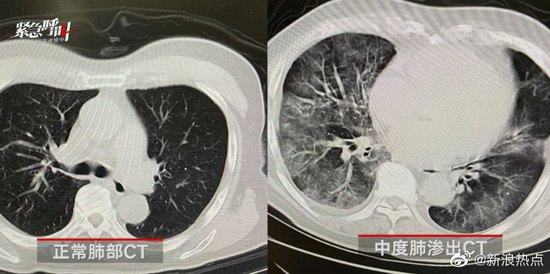

我们先来看一下正常肺的样子。

就这样:

但是如果肺被病毒感染了,里面就会有很多的液体,这个时候再去拍片,肺部看上去就是模模糊糊,云雾状的白色(下图右

这就是我们俗称的“白肺”。

白色越多,就说明越严重。

如果新冠感染后,出现“大白肺”,就意味着肺部已经被病毒严重侵蚀了。